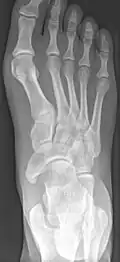

X-ray of the foot showing an accessory navicular bone

An accessory navicular bone is an accessory bone of the foot that occasionally develops abnormally in front of the ankle towards the inside of the foot. This bone may be present in approximately 2-14% of the general population and is usually asymptomatic.[1][2][3] When it is symptomatic, surgery may be necessary.

The Geist classification divides the accessory navicular bones into three types.[3]

• Type 1: An os tibiale externum is a 2–3 mm sesamoid bone in the distal posterior tibialis tendon. Usually asymptomatic.

• Type 2: Triangular or heart-shaped ossicle measuring up to 12 mm, which represents a secondary ossification center connected to the navicular tuberosity by a 1–2 mm layer of fibrocartilage or hyaline cartilage. Portions of the posterior tibialis tendon sometimes insert onto the accessory ossicle, which can cause dysfunction, and therefore, symptoms.

• Type 3: A cornuate navicular bone represents an enlarged navicular tuberosity, which may represent a fused Type 2 accessory bone. Occasionally symptomatic due to bunion formation.